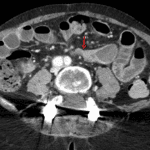

- Multiple dilated loops of small bowel throughout the abdomen measuring up to 3.5 cm in diameter with a transition to normal caliber in the distal ileum

- The jejunum and ileum are on opposite sides of the abdomen (jejunum on the right and ileum on the left) with a sac-like configuration of the displaced ileal loops and associated edema in the ileal mesentery

- Closed-loop small bowel obstruction

Small bowel obstruction with transition point in the distal ileum. Configuration of displaced loops of jejunum and ileum raises concern for closed loop obstruction related to an internal hernia. No evidence of bowel ischemia.